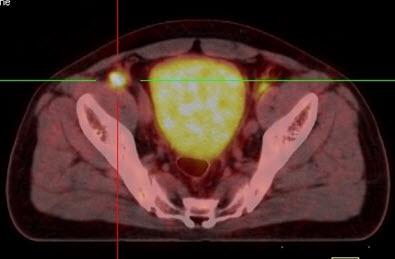

Hình 5. Bệnh nhân Nguyễn X.T., nam, 58 tuổi. Chẩn đoán: U lympho ác tính không Hodgkin, giải phẫu bệnh: WF6. Hình PET cho thấy tổn thương ở phổi, hạch, xương, tuyến thượng thận hai bên (mũi tên). Hình CT và PET/CT cho thấy tổn thương tăng hấp thu FDG tại vị trí tuyến thượng thận hai bên (mũi tên), max SUV=11,34.